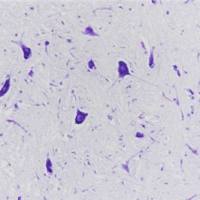

免疫组化是应用免疫学基本原理——抗原抗体反应,即抗原与抗体特异性结合的原理,通过化学反应使标记抗体的显色剂(荧光素、酶、金属离子、同位素) 显色来确定组织细胞内抗原(多肽和蛋白质),对其进行定位、定性及定量的研究,称为免疫组织化学技术(immunohistochemistry)或免疫细胞化学技术(immunocytochemistry)。

免疫组化的分类: 免疫组织化学技术按照标记物的种类可分为免疫荧光法、免疫酶法、免疫铁蛋白法、免疫金法等。

服务内容:包含抗体,包埋,切片,染色以及拍照。(每个样本提供一张照片包含阳性面积)加拍另外计费